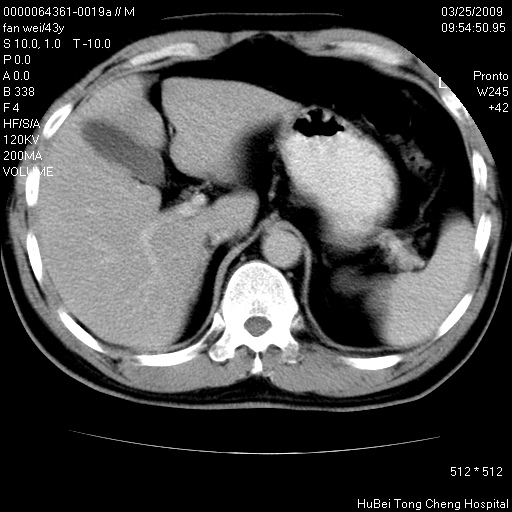

患者 男,43岁。左侧腰部不适两天。平素健康。无家族遗传病史。

腹部彩超提示:1)轻度脂肪肝。2)左肾多发囊性占位性病变;建议行进一步检查。

临床诊断:左肾多发囊性占位性病变,性质待定(多发肾囊肿?)。

双肾ct轴位平扫+增强扫描(层厚10mm,螺距1.0,重建间隔10mm),图像如下: